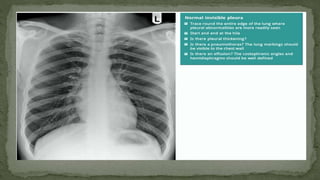

4. PLEURA AND PLEURAL SPACES

• The pleura are only visible when there is an abnormality

present.

• This can be due to pleural thickening and fluid or air

accumulating in the pleural spaces.

• Lung markings should reach the thoracic wall

5. COSTOPHRENIC ANGLE AND RECESS

• The costophrenic recesses are formed by hemidiaphragms

and chest wall.

• They contain the rim of the lung bases which lie over the

dome of each hemidiaphragm.

• These angles are known as the costophrenic angles.

• Costophrenic angles should form acute angles that are

sharp to the point.